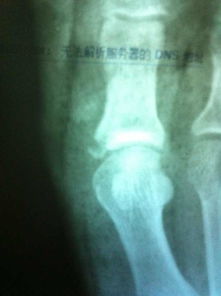

拆除石膏后,許多病人感到關(guān)節(jié)不舒服,有疼痛感。因?yàn)殛P(guān)節(jié)長(zhǎng)期固定后,關(guān)節(jié)內(nèi)粘連,軟組織攣縮,所以活動(dòng)時(shí)關(guān)節(jié)不適是正?,F(xiàn)象。此外,拆除石膏后,病人必須照 X 線片,以便明確骨折愈合的情況。若骨折尚未愈合,千萬(wàn)不要伯麻煩,還需要重新固定。若骨折已愈合,此時(shí)必須逐步加強(qiáng)功能鍛煉。同時(shí)由于此時(shí)骨折愈合尚不牢固,而且長(zhǎng)期固定后,骨代謝有所改變,骨質(zhì)明顯疏松,所以應(yīng)當(dāng)避免某些可能導(dǎo)致再骨折的動(dòng)作,更應(yīng)避免再次外傷。再次骨折后,骨折愈合更為困難,而且需要再固定,關(guān)節(jié)的功能將會(huì)受到無(wú)法挽回的影響。當(dāng)然也應(yīng)當(dāng)消除不必要的顧慮,有些病人由于害怕再骨折,拆除石膏后,不敢活動(dòng)關(guān)節(jié),不敢進(jìn)行鍛煉,這樣反而會(huì)影響骨折愈合。影響肢體功能的恢復(fù)。